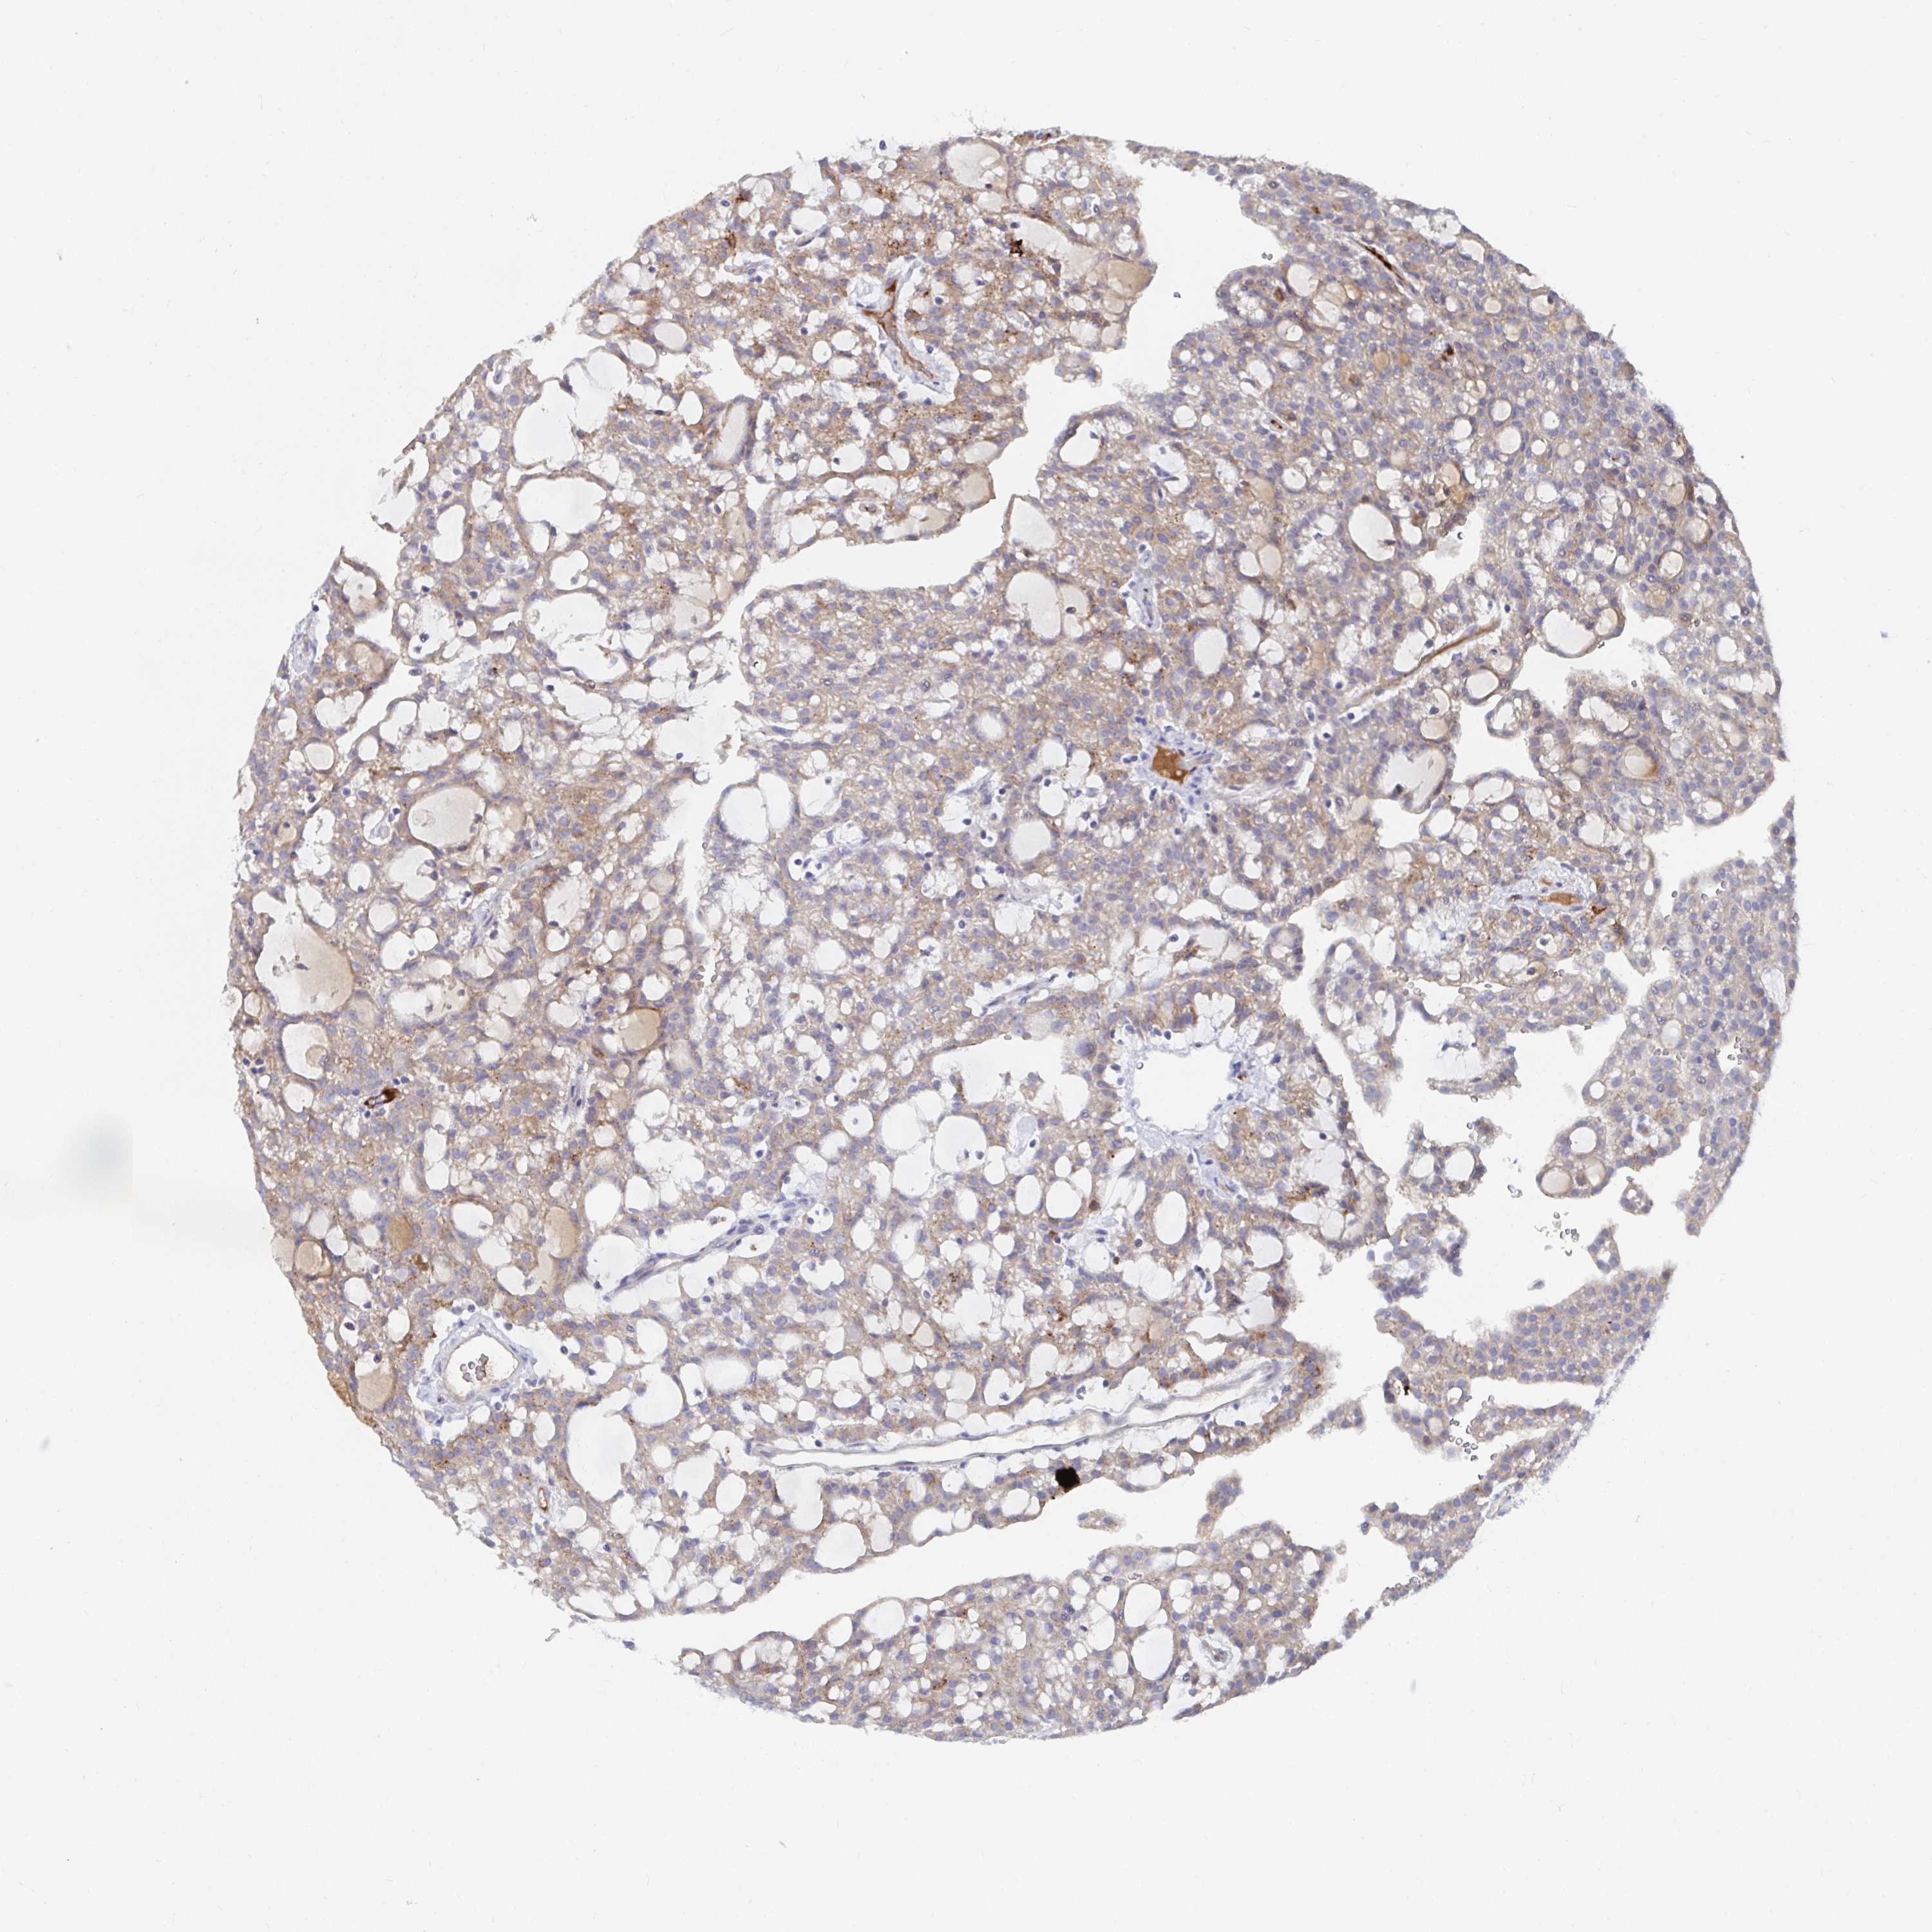

KIDNEY RENAL CLEAR CELL CARCINOMA (TCGA) - Interactive survival scatter ploti

The Survival Scatter plot shows the clinical status (i.e. dead or alive) for all individuals in the patient cohort, based on the same data that underlies the corresponding Kaplan-Meier plots. Patients that are alive at last time for follow-up are shown in blue and patients who have died during the study are shown in red.

The x-axis shows the expression levels (FPKM) of the investigated gene in the tumor tissue at the time of diagnosis. The y-axis shows the follow-up time after diagnosis (years). Both axes are complimented with kernel density curves demonstrating the data density over the axes. The top density plot shows the expression levels (FPKM) distribution among dead (red) and alive patients (blue). The right density plot shows the data density of the survived years of dead patients with high and low expression levels respectively, stratified using the cutoff indicated by the vertical dashed line through the Survival Scatter plot. This cutoff is automatically defined based on the FPKM cutoff that minimizes the p-score. The cutoff can be changed by dragging the vertical line or by entering a cutoff value in the square labeled "Current cut-off".

Under the Survival Scatter plot the p-score landscape (black curve; left axis) is shown together with dead median separation (red curve; right axis). Dead median separation is the difference in median mRNA expression between patients who have died with high and low expression, respectively. It is calculated as follows: median FPKM expression of dead patients with high expression - median FPKM expression of dead patients with low expression. This is intended to aid the user in visually exploring custom cutoffs and the associated p-scores and dead median separation.

Individual patient data is displayed and can be filtered by clicking on one or more of the category buttons on the top of the page. Categories describing expression level and patient information include: high, low, alive, dead, female, male and tumor stages. The scale of the x-axis can be toggled between linear and log-scale by clicking on the "x log" button. Mouse-over function shows TCGA ID, patient information and mRNA expression (FPKM) for each patient.

& Survival analysisi

Kaplan-Meier plots summarize results from analysis of correlation between mRNA expression level and patient survival. Patients were divided based on level of expression into one of the two groups "low" (under cut off) or "high" (over cut off). X-axis shows time for survival (years) and y-axis shows the probability of survival, where 1.0 corresponds to 100 percent.

KCNK5 is validated prognostic, high expression is favorable in Kidney Renal Clear Cell Carcinoma (TCGA)

Best expression cut offi

Based on the FPKM value of each gene, patients were classified into two groups and association between prognosis (survival) and gene expression (FPKM) was examined. The best expression cut-off refers the FPKM value that yields maximal difference with regard to survival between the two groups at the lowest log-rank P-value. Best expression cut-off was selected based on survival analysis .

When clicking on this number, the vertical dashed line indicating cut-off, the interactive survival plot, and the Kaplan-Meier curve will be adjusted to show results based on the best expression cut-off.

: 10.32

TCGA RNA samplesi

RNA-seq data is reported as average FPKM (number Fragments Per Kilobase of exon per Million reads), generated by the The Cancer Genome Atlas (TCGA) .

Normal distribution across the dataset is visualized with box plots, shown as median and 25th and 75th percentiles. Points are displayed as outliers if they are above or below 1.5 times the interquartile range. FPKM values of the individual samples are presented next to the box plot.

Average pTPM 14.0

Number of samples 521